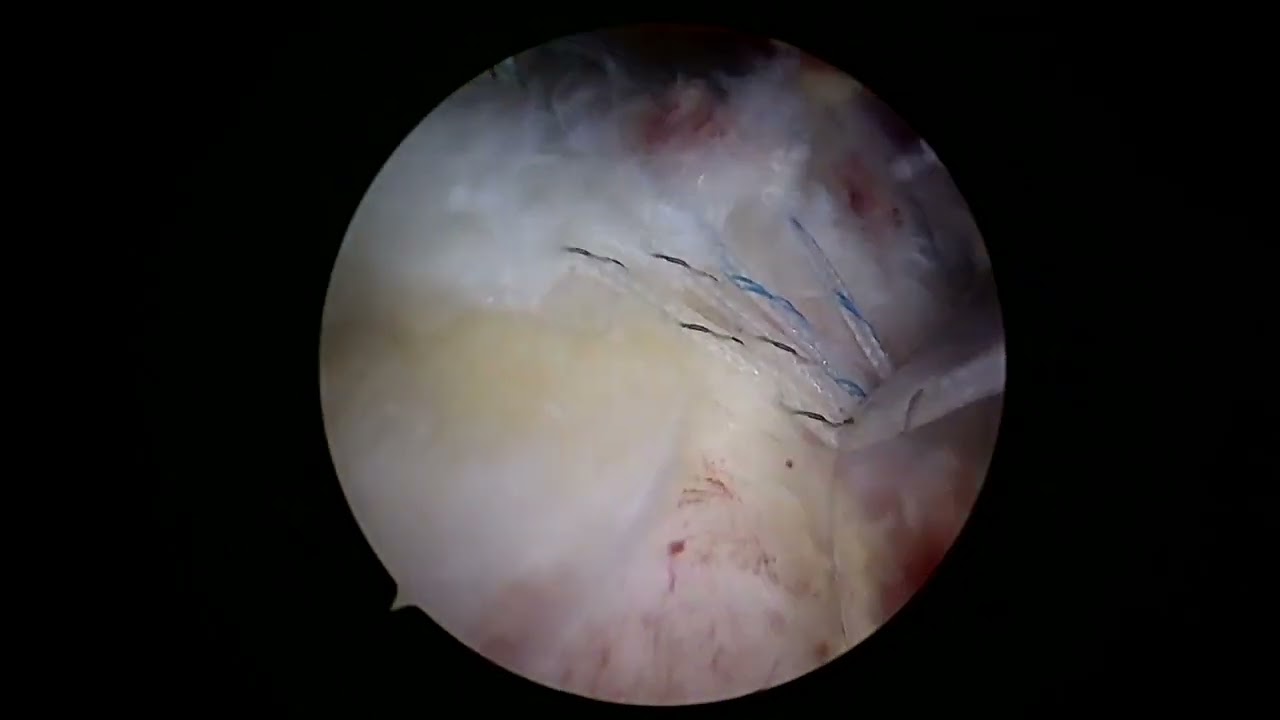

Następnie odbywałem podspecjalizację w zakresie artroskopii i rekonstrukcji barku, łokcia i kolana w Królewskim Szpitalu Ortopedycznym (The Royal Orthopaedic Hospital) w Northfield oraz w Centrum Urazowym Uniwersyteckiego Szpitala Królowej Elżbiety (Queen Elizabeth Hospital) w Birmingham.

Zdjęcia i filmy